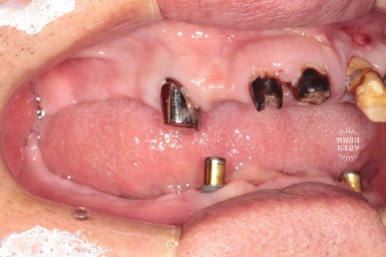

왼쪽: 위 앞니 보철물 + 부분틀니, 오른쪽: 임플란트 오버덴쳐???

사용하시던 틀니를 보아하니...

위턱에 사용하시던 보철물은 다 부러져 있었고,

아래턱에 사용하시던 틀니는 오버덴쳐인 줄 알았더니 오버덴쳐가 아니었어요.

틀니에 구멍 보이시나요?? 그냥 적당한 자리에 임플란트 두개 심고

틀니에 구멍을 내서 껴놓으셨더라구요.........

이런건 절대 교과서적인 치료가 아닙니다.

얼마나 환자분이 힘드셨을까요? ㅠㅠ